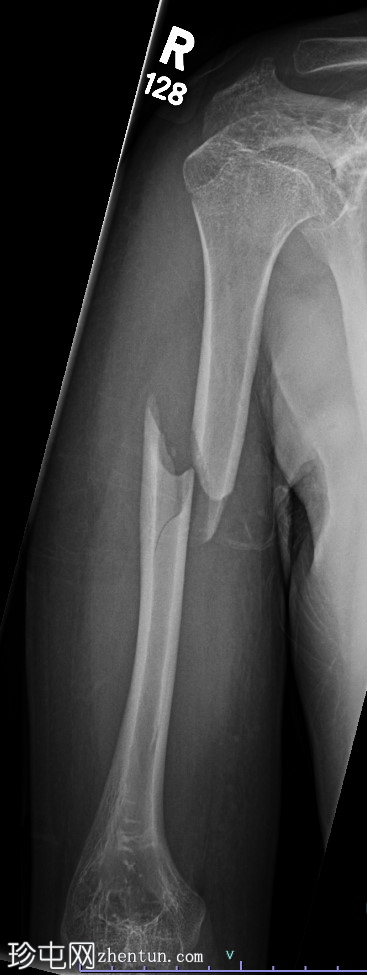

前臂X光片,2个视角 - 右侧

X光片

侧位

右侧桡骨弯曲畸形,伴有骨骼发育不良,桡骨远端桡骨倾斜度(尺骨倾斜度)增大,尺骨变异为负值。

腕骨弧形完整,桡骨和尺骨之间无腕骨楔入征兆。

前臂无急性骨折。

周围软组织中度水肿。